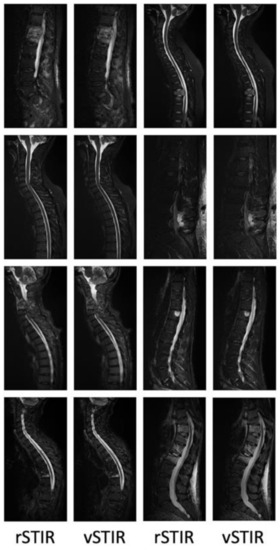

3. Results